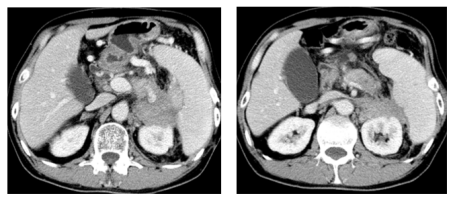

2023-08-29胸部CT未见转移,腹部CT:结肠脾曲术后,肝多发转移,胰腺区,肾前,脾内侧多发转移,病变包绕胰腺及脾动脉静脉,胃底及左上腹静脉迂曲扩张,肝门区,肠系膜内及腹膜后,左侧髂血管旁周围多发肿大淋巴结。左肾周受侵。

image.png

图1 2023年8月29日检查结果